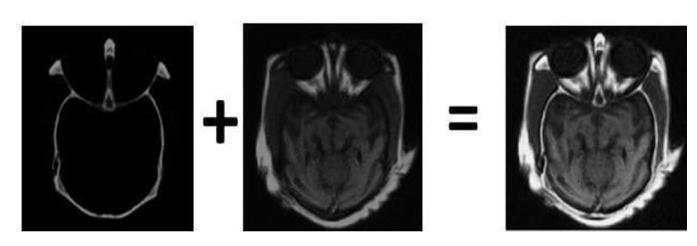

Fig.7.3.1ComputedTomographyScan

Fig.7.3.2Magneticresonanceimaging

Fig.7.3.3FusedImage1

Fig.7.3.4FusedImage2